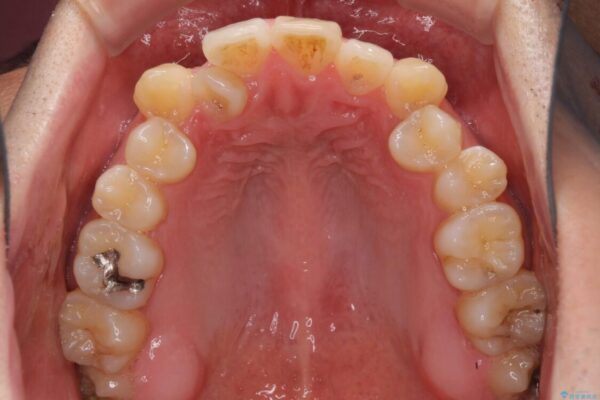

治療前

• 左右の八重歯が気になる ワイヤー装置での咬み合わせ改善 治療前画像